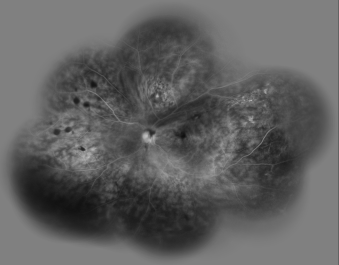

Dilated posterior segment examination of the right eye showed 1+ to 2+ cells in the anterior vitreous and subretinal exudation which involved macula and premacular membrane (Figure 1 [Fig. 1]). Moreover, in the periphery, an elevated pink vascular mass with areas of surrounding subretinal fluid and lipid accumulation was seen. Dilated tortuous feeder vessels, as seen with retinal capillary hemangioma, were not observed. Fluorescein angiogram showed diffuse telangiectatic vessels with leakage (Figure 2 [Fig. 2]). Fundus examination in the left eye showed subretinal old refractile exudations in the periphery and macula as well as premacular and optic disc fibrous proliferation with macular dragging. Fluorescein angiography revealed optic disc leakage and diffuse perivascular leakage (Figure 3 [Fig. 3] and Figure 4 [Fig. 4]). In macular optical coherence tomography (OCT), in the right eye severe macular thickening with central thickness of 764 µm and subretinal fluid were seen, and in the left eye macular atrophy and intra- and subretinal hyper-reflective material were observed (Figure 5 [Fig. 5] and Figure 6 [Fig. 6]). The findings were consistent with vasoproliferative tumor associated with macular edema and retinal exudation. Various therapeutic methods were discussed, and the patient was treated with three monthly injections of bevacizumab (1.25 mg in 0.05mL) in the right eye. After 3 months, macular thickening and subretinal exudation were significantly decreased, retinal detachment overlying the vasoproliferative tumor had resolved, and the tumor appeared less vascularized with fibrotic changes. Macular thickness decreased to 354 µm and vision improved to 3/10 (Figure 7 [Fig. 7]). After 6 months, the condition was stable and the follow-up interval was decided to be 3 months.

Figure 1: Posterior pole of right eye with subretinal exudation which involved macula with premacular membrane